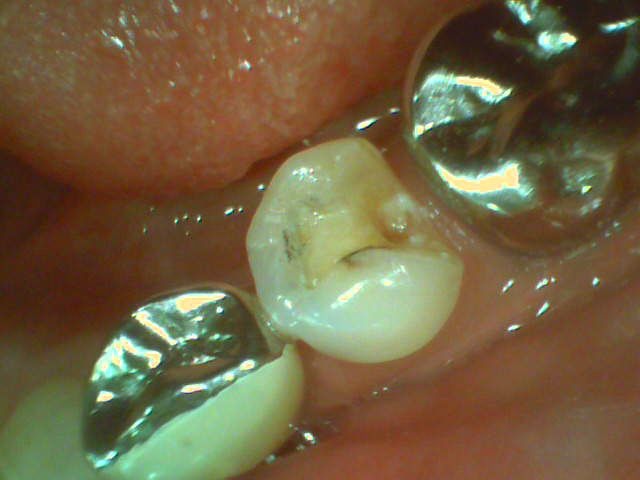

先日、メタルインレーが外れてしまった患者さんが来院されました。

取れてしまった物はなく、新しい治療が必要になります。この方は以前から審美障害を訴えられており、メタルフリーの治療を御希望なされましたので、歯質削除量の少ないダイレクトボンディングを選択いたしました。下記のように自然に修復することができました。